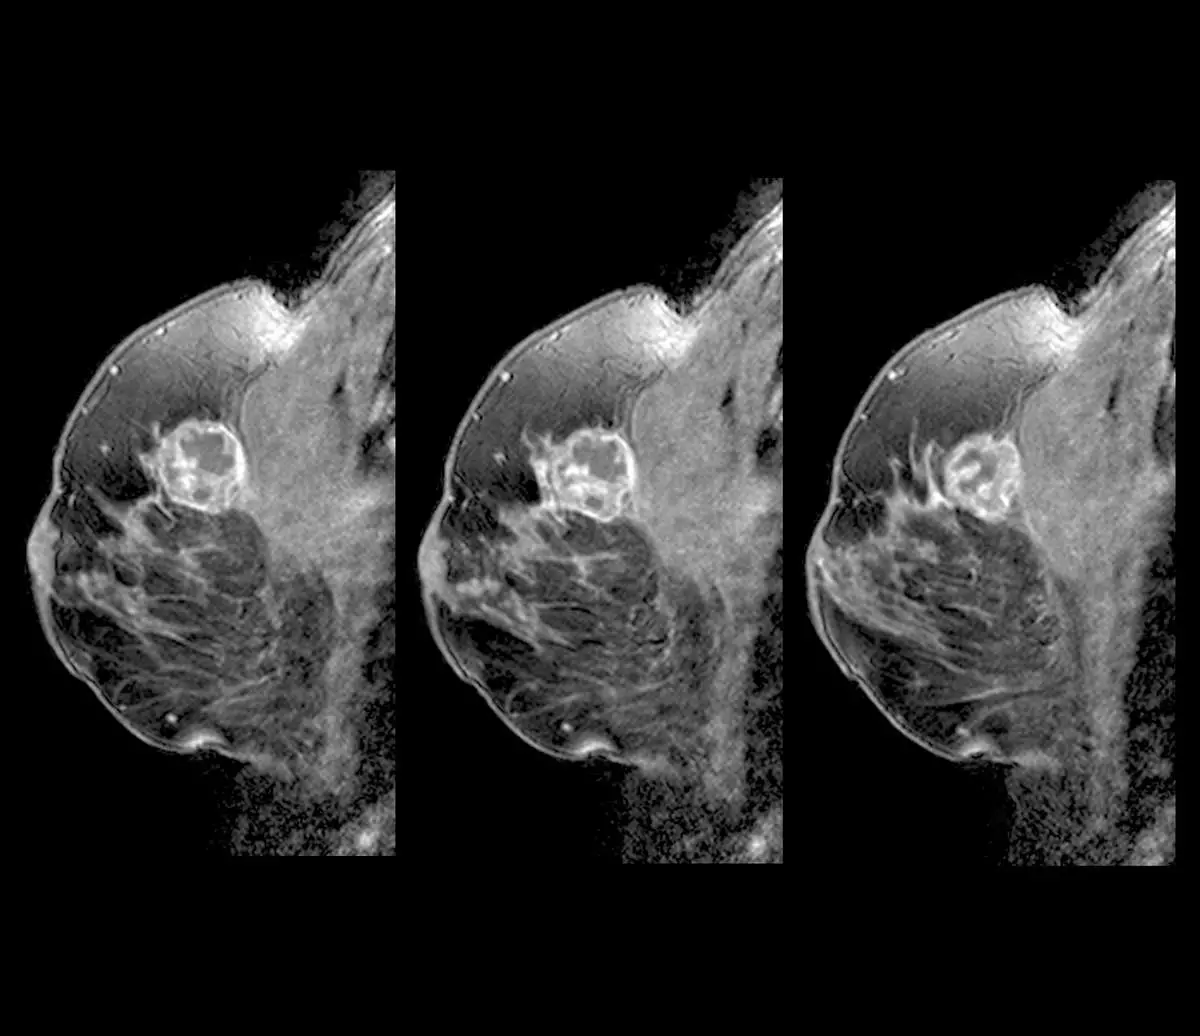

유방 MRI 검사 결과. 기사의 내용과 직접적 연관이 없는 사진./사진=클립아트코리아